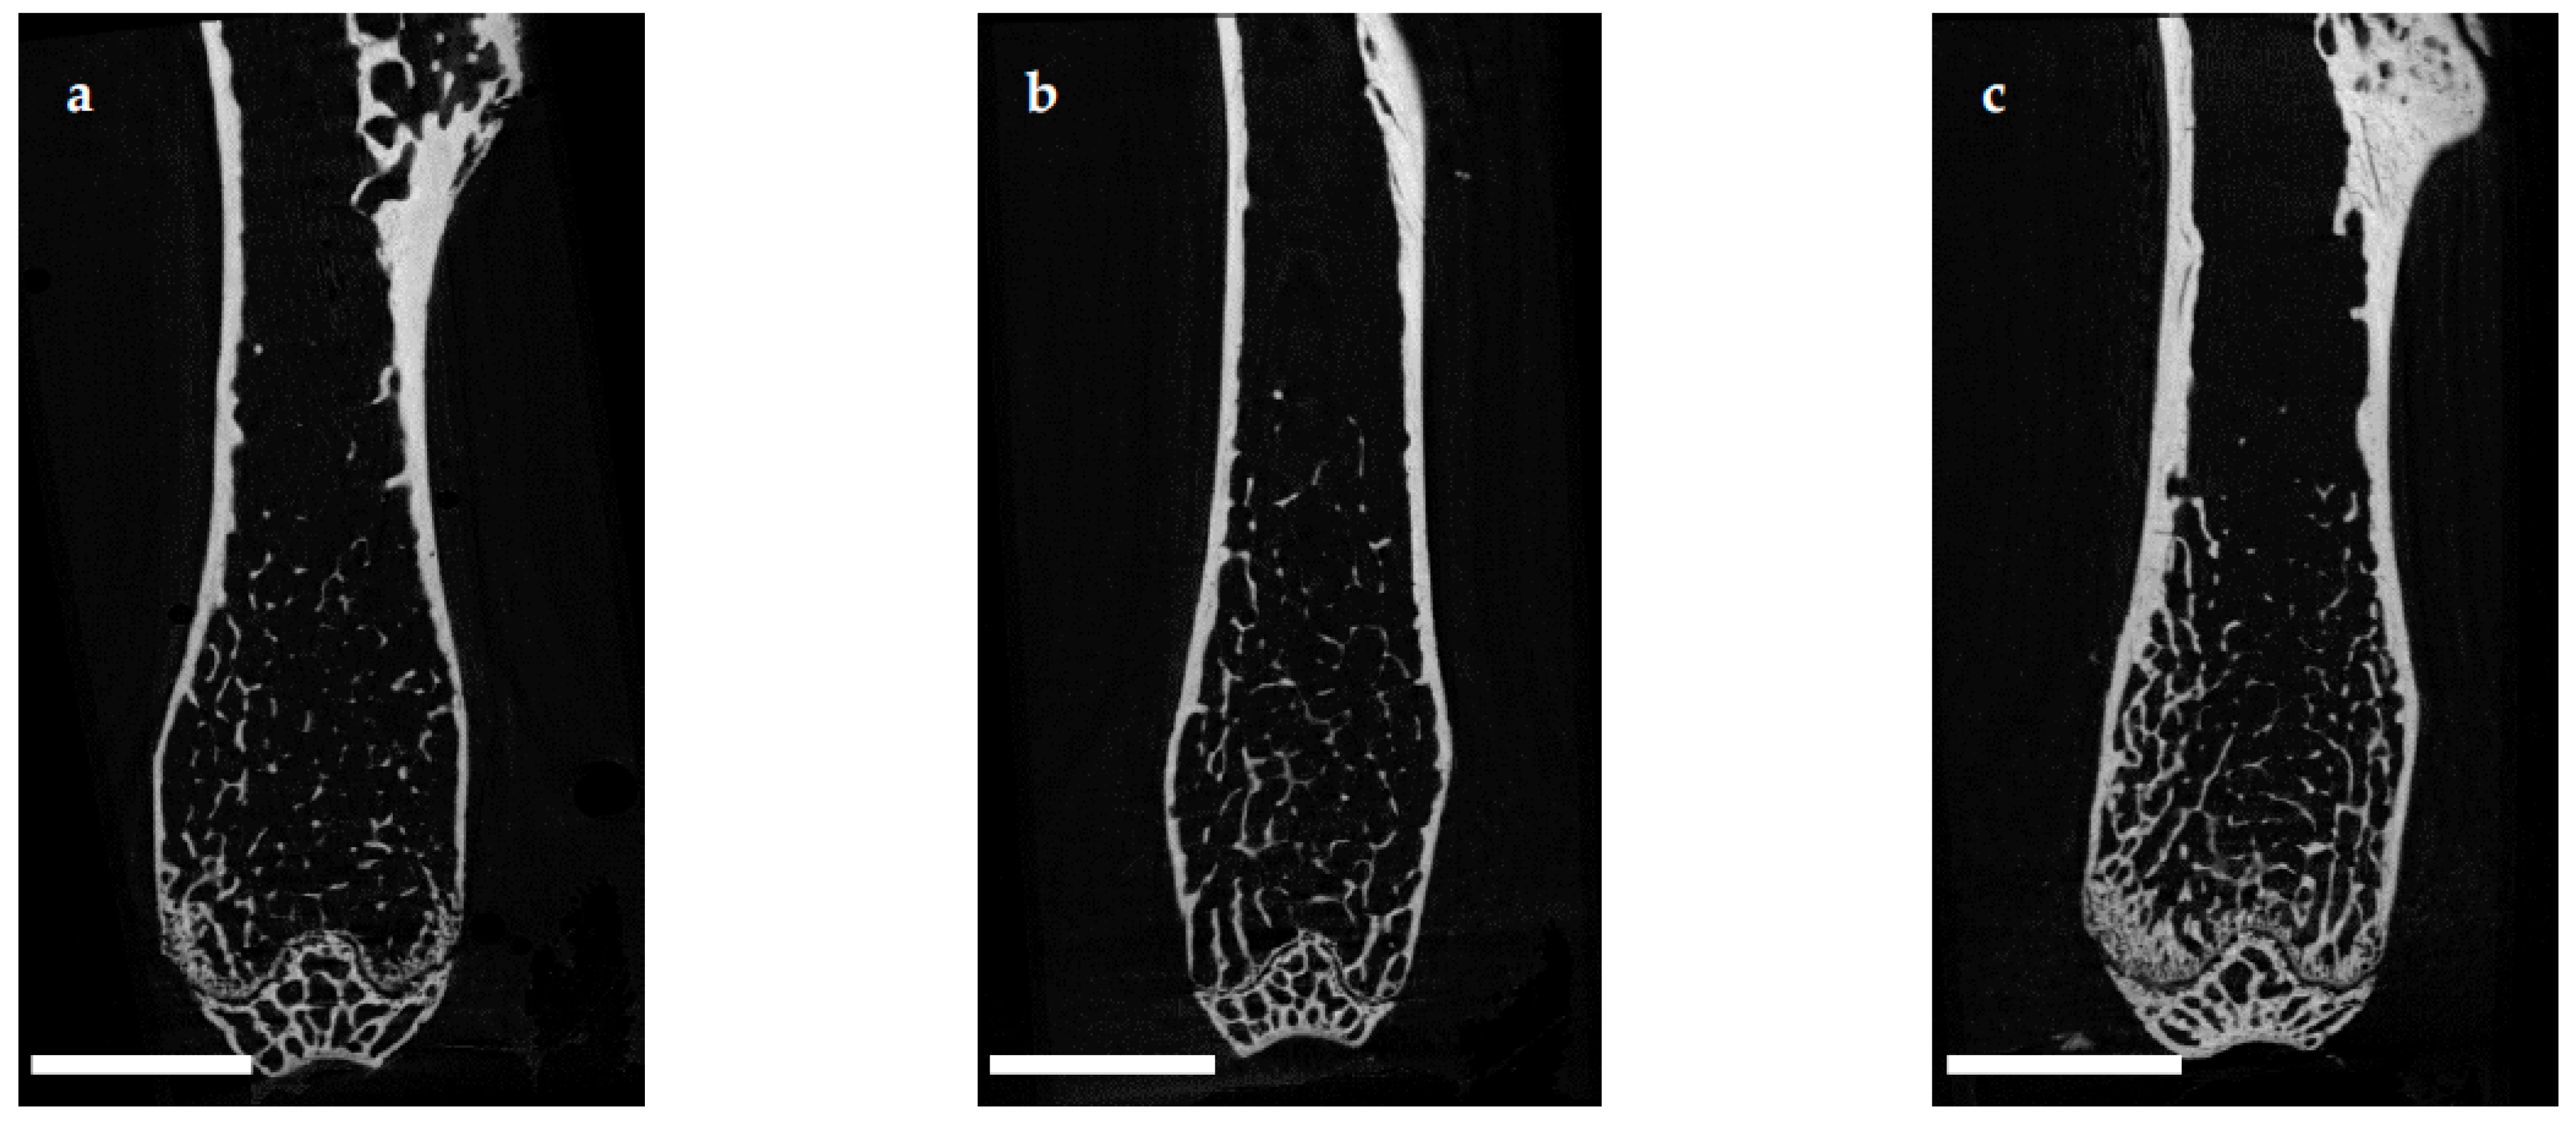

The microarchitecture of the femoral cortex was analyzed at mid diaphysis and distal diaphysis by micro computed tomography (µCT). Two-dimensional example images from µCT scans (Figure 3) demonstrated a loss of cortical as well as trabecular bone mass following (a) EAO or (b) treatment with adjuvant alone, compared to (c) untreated mice.

Figure 3. Two-dimensional images from µCT scans of distal femora (scale bar 2 mm). Mice were immunized with (a) testicular homogenate in adjuvant (EAO), (b) adjuvant alone or (c) remained untreated.